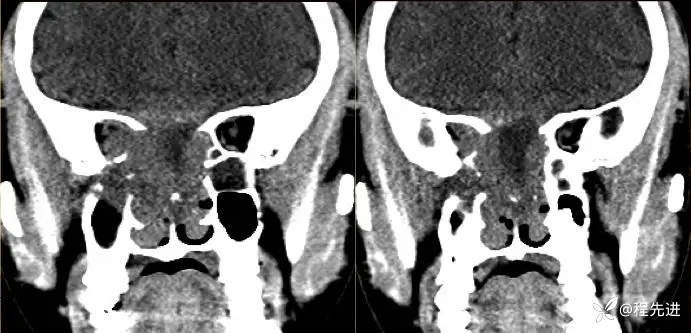

【患者信息】:男,24岁

【现病史及既往史】:患者1月前无明显诱因出现右脸麻木,之后出现复视,20天前发出现右眼失明伴头痛

CT:

增强: